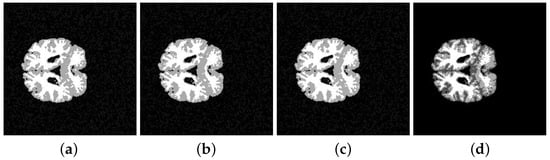

| Segmented Image | K-means | FCM | SFCM | KFCM |

|---|---|---|---|---|

| 202-3 original | 0.5842 | 0.5850 | 0.5832 | 0.5889 |

| 202-3 with noise | 0.5859 | 0.5873 | 0.5856 | 0.5845 |

| 205-3 original | 0.5793 | 0.5781 | 0.5758 | 0.5761 |

| 205-3 with noise | 0.5763 | 0.5787 | 0.5761 | 0.5782 |